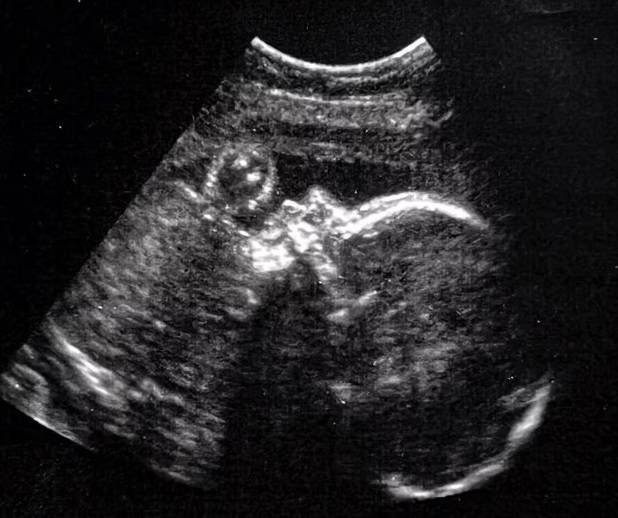

أجرى فريق من الأطباء الأمريكيين بمستشفى بوسطن للأطفال ومستشفى ماساتشوستس العام عملية جراحية دقيقة هي الأولى من نوعها لجنين شخصت حالته بتشوه جالينوس في الأسبوع 30 من الحمل.

وقال د. غاري ساتو، طبيب القلب في جامعة كاليفورنيا، لوس أنجليس: «حدد الأطباء التشوه في جنين في الأسبوع الثلاثين من الحمل باستخدام التصوير بالرنين المغناطيسي، ثم شرع الجراحون في فتح دماغ الجنين لزرع قطعة من الدهون بالقرب من الشريان من شأنها وقف تدفق الدم».